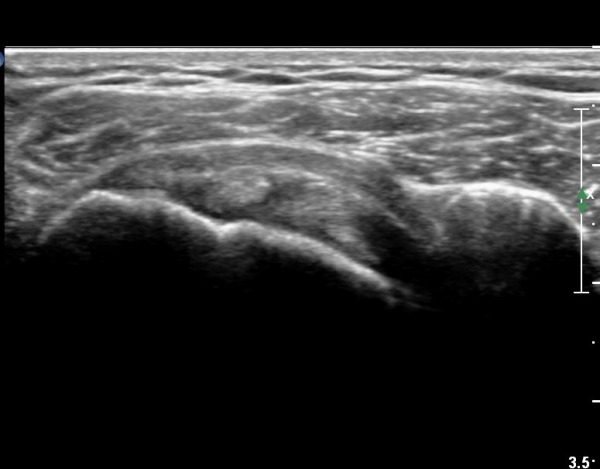

ŽÃËÀÚ¸¦ ¾à°£ °ßºÀ ¸»´ÜÀ¸·Î ³»¸®³ª ¿À±¸µ¹±â°ßºÀÀδëÀÇ ¼®È¸È­°¡ °üÂûµÈ´Ù(»çÁø 2).